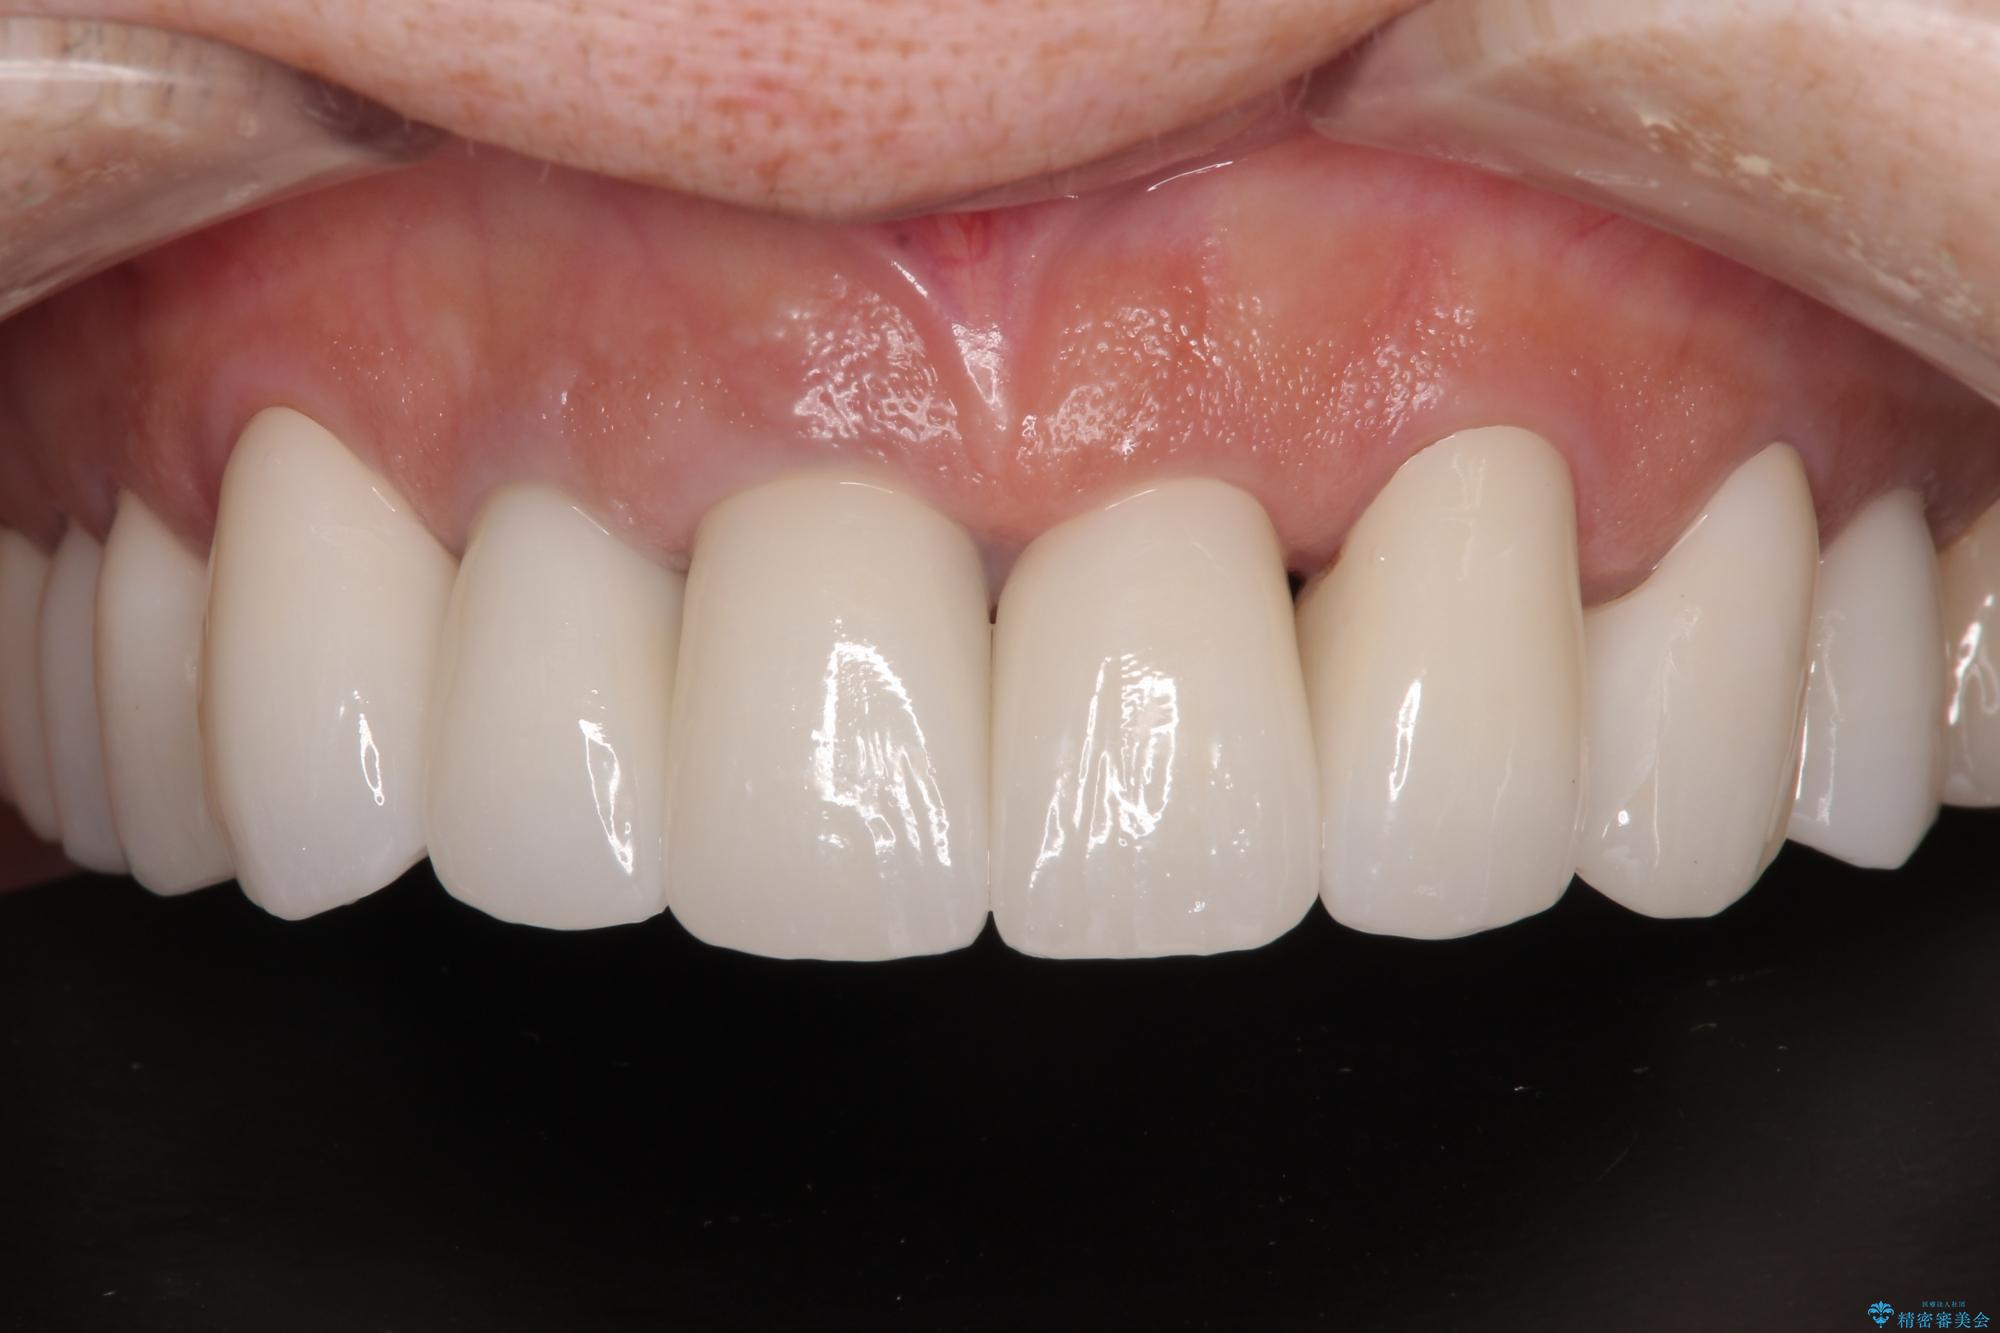

不釣り合いで境目の露出した前歯 オールセラミッククラウンによる審美歯科治療

20年以上前から、むし歯になったり詰め物が欠けたりする度に部分的に処置を行ってきたそうですが、この際統一感のある前歯にしたいとのことで、上顎前歯9本をオールセラミッククラウンによる補綴治療を行うこととしました。

色調が統一されるだけでなく、歯肉ラインに見えていた茶色の境目も綺麗に改善されました。